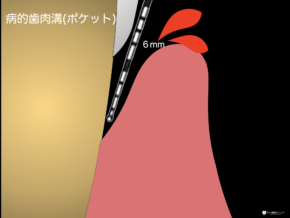

歯周病治療は、歯周ポケットと呼ばれる病的にできた歯と歯ぐきの間の隙間を浅くすることが『治療のゴール』であり、予防ステージである『メインテナンスのスタート』となります。

歯周ポケットと呼ばれる歯と歯ぐきの境目の深さと、そこからの出血の有無を検査します。